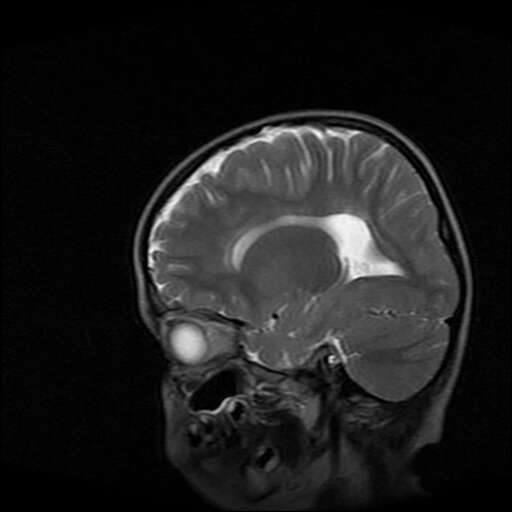

女,7岁,三岁才说话、走路。现智力尚可,走路不稳。临床怀疑大脑发育不全。

考虑 脑白质发育不良

脑折质变薄,双侧侧脑室稍扩张,支持考虑脑折质发育不良

侧脑室周围白质软化症。

考虑胼胝体发育不全,髓鞘形成不良。

支持考虑胼胝体发育不全,髓鞘形成不良。

脑裂畸形伴灰质异位

侧脑室周围白质数量减少,侧脑室不对称性扩大,左侧侧脑室后角呈方形改变,脑沟加深,结合临床考虑脑室周围白质软化症(pvl)。期待结果!

只看出灰质异位

支持脑白质发育不良。